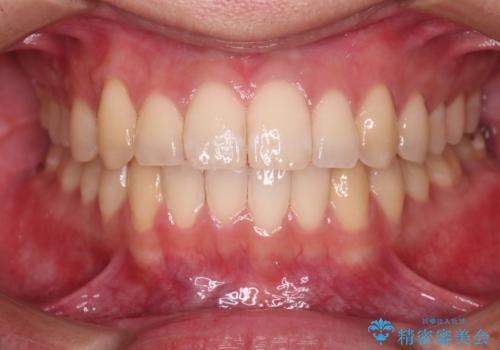

【クリア装置】八重歯とがたつきを綺麗に